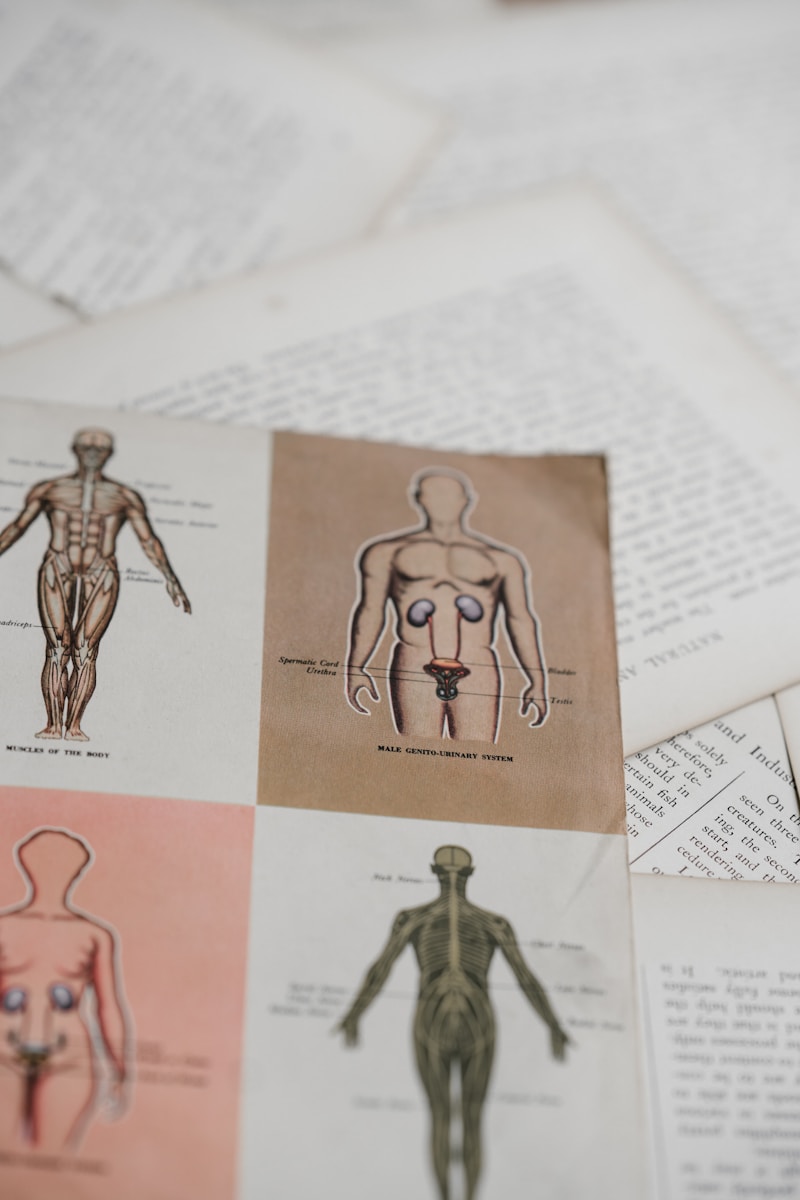

9. Spermie nájdu vajíčko podľa vône

Spermie majú čuchové receptory, ktoré ich vedú k vajíčku pomocou jeho vône. Tento fascinujúci mechanizmus je stále predmetom výskumu a môže výrazne ovplyvniť medicínu, napríklad pri vývoji novej antikoncepcie.